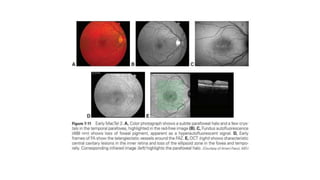

Macular Telangiectasia Type 2

• the most common form

• progressive bilateral idiopathic neurodegenerative disease of the macular,

parafoveal, ret ina.

• Characteristic findings begin to appear in the fifth to seventh decades of

life

₋ a reduced foveolar reflex

₋ loss of ret i nal transparency (ret in al graying)

₋ superficial ret i nal crystalline deposits

₋ mildly ectatic capillaries

₋ slightly dilated blunted venules

₋ progression to pigment hyperplasia, and

₋ foveal atrophy

• Subreti n al neovascularization

• dysfunction of both neural and vascular reti n al ele ments,

suggesting that a macular Müller cell defect plays an essential role in

the pathogenesis of this disease

• FA shows telangiectatic vessels and usually leak.

• OCT

₋ shows a thinned central macular ret ina, including the fovea; within the inner

foveal layers,

₋ oblong cavitations are pres ent in which the long axis is parallel to the ret i nal

surface

• To date, t here is no FDA-approved, effective treatment of MacTel 2

• Intravitreal anti- VEGF therapy is used for the management of active

subreti n al neovascularization with associated hemorrhage or

exudation